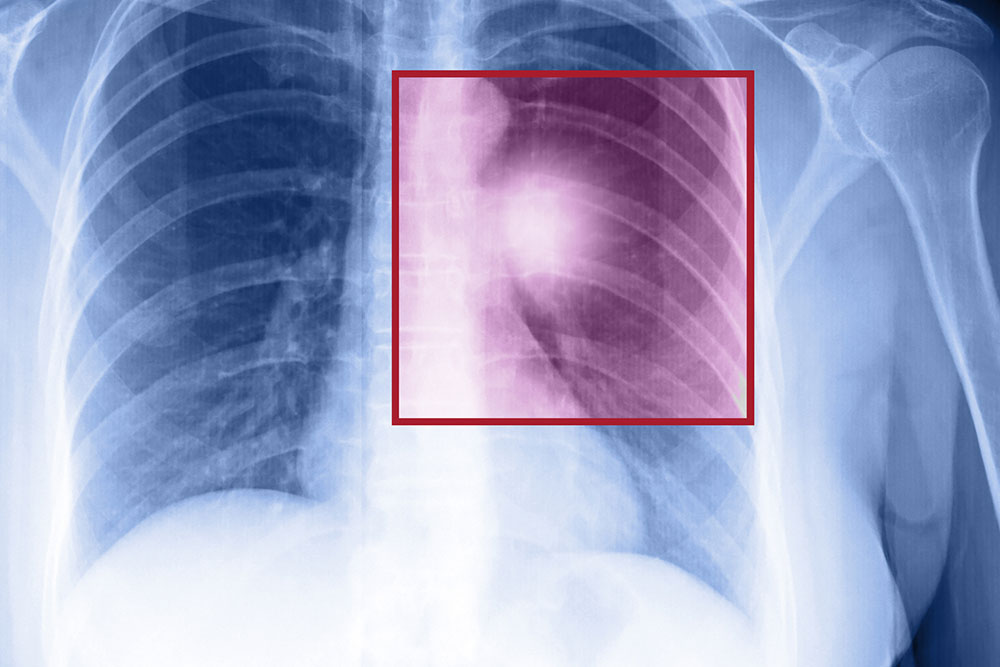

- Chest X-ray which provides detailed images of the lungs.